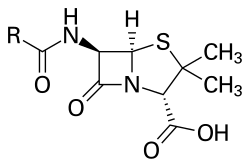

It is unclear whether or not acute proliferative glomerulonephritis (i.e., poststreptococcal glomerulonephritis) can be prevented with early prophylactic antibiotic therapy, with some authorities arguing that antibiotics can prevent development of acute proliferative glomerulonephritis[14]